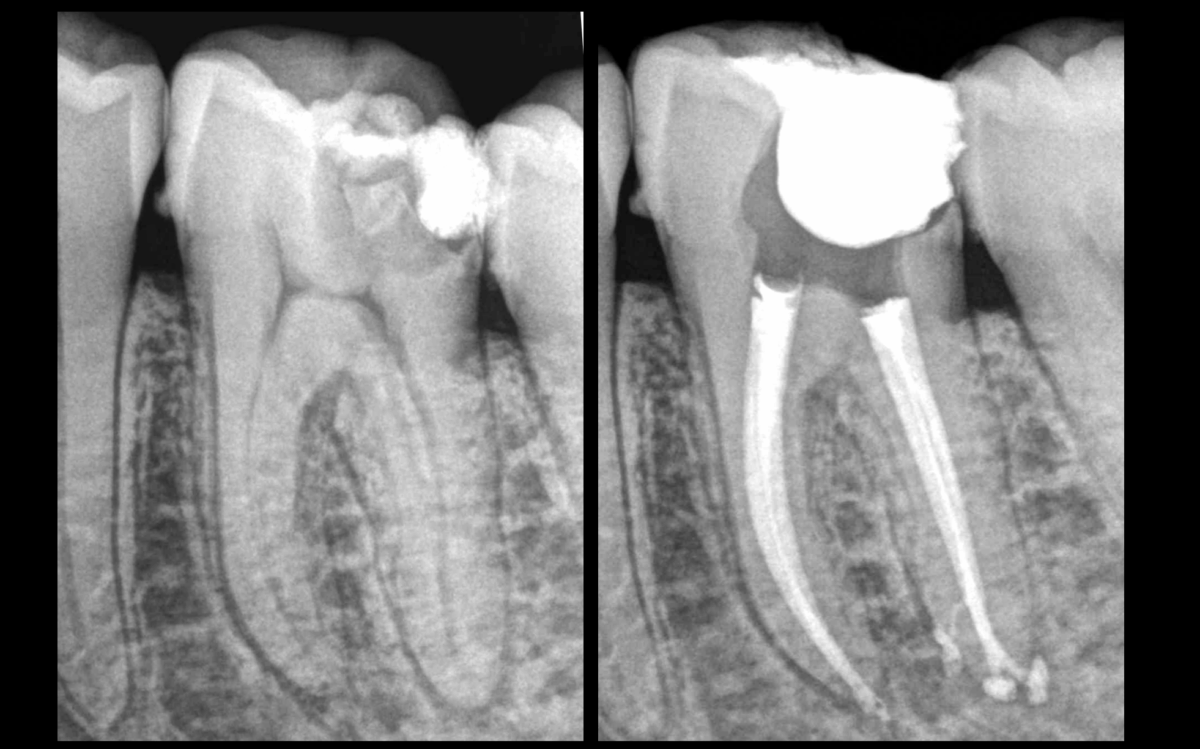

➡️ 𝐋𝐞𝐬 𝐫𝐚𝐜𝐢𝐧𝐞𝐬 𝐦𝐞́𝐬𝐢𝐚𝐥𝐞𝐬 𝐝𝐞𝐬 𝐦𝐨𝐥𝐚𝐢𝐫𝐞𝐬 𝐦𝐚𝐧𝐝𝐢𝐛𝐮𝐥𝐚𝐢𝐫𝐞𝐬 𝐩𝐫𝐞́𝐬𝐞𝐧𝐭𝐞𝐧𝐭 𝐥𝐚 𝐩𝐥𝐮𝐩𝐚𝐫𝐭 𝐝𝐮 𝐭𝐞𝐦𝐩𝐬 𝐮𝐧𝐞 𝐜𝐨𝐧𝐜𝐚𝐯𝐢𝐭𝐞́ 𝐞𝐧 𝐝𝐢𝐬𝐭𝐚𝐥.

📉 𝐔𝐧𝐞 𝐜𝐨𝐧𝐢𝐜𝐢𝐭𝐞́ 𝐝𝐞 𝟔% 𝐟𝐚𝐢𝐭 𝐩𝐞𝐫𝐝𝐫𝐞 𝐩𝐥𝐮𝐬 𝐝𝐞 𝟔𝟎% 𝐝𝐞 𝐥’é𝐩𝐚𝐢𝐬𝐬𝐞𝐮𝐫 𝐝𝐞 𝐝𝐞𝐧𝐭𝐢𝐧𝐞 𝐫𝐚𝐝𝐢𝐜𝐮𝐥𝐚𝐢𝐫𝐞, entre le canal travaillé et la surface radiculaire externe de la concavité.